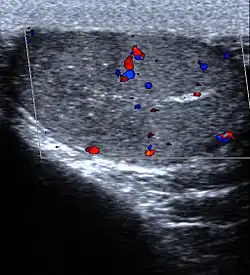

Infarction of the lung due to a pulmonary embolism